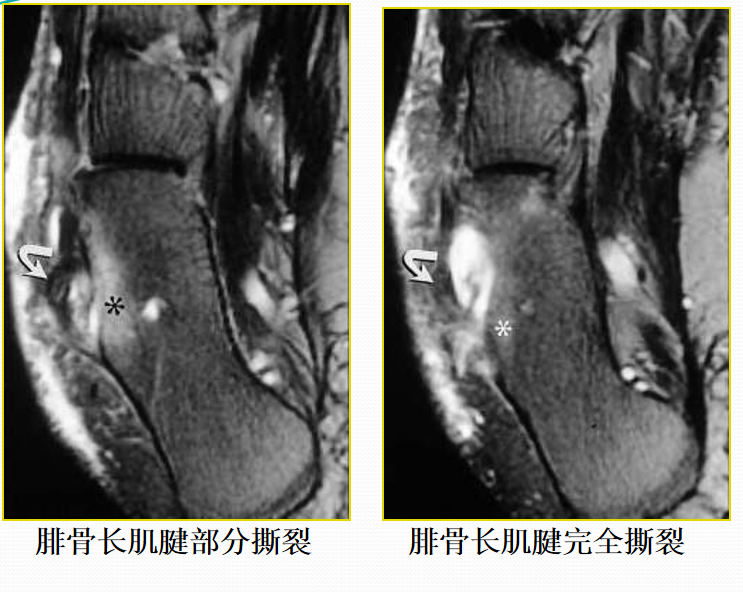

胫前、胫后肌腱撕裂

病因病理机制:

• 好发于中年人,胫骨前肌腱多见于登山运动员。

• 类风湿性关节炎、有副舟骨患者好发。

• 足踝运动障碍、疼痛。

• 胫骨后肌腱是维持足弓的重要力量,撕裂后易出现扁足。

MR表现:

• 胫骨前肌腱较少发生撕裂,一旦发生,多为全肌腱损伤

• 胫骨后肌腱出现横截撕裂或纵行撕裂

• 肌腱增粗,原本椭圆形的肌腱横断面变成圆形

• 可为横向或纵向撕裂;完全或部分撕裂

• 相应的腱鞘积液和鞘膜增厚

• 邻近关节见骨关节炎表现